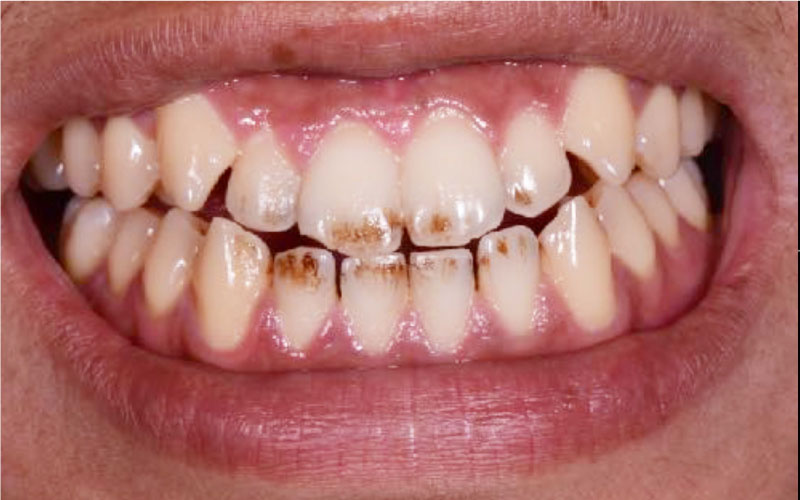

Before

• 牙齒染色

• 茶垢、菸垢附著